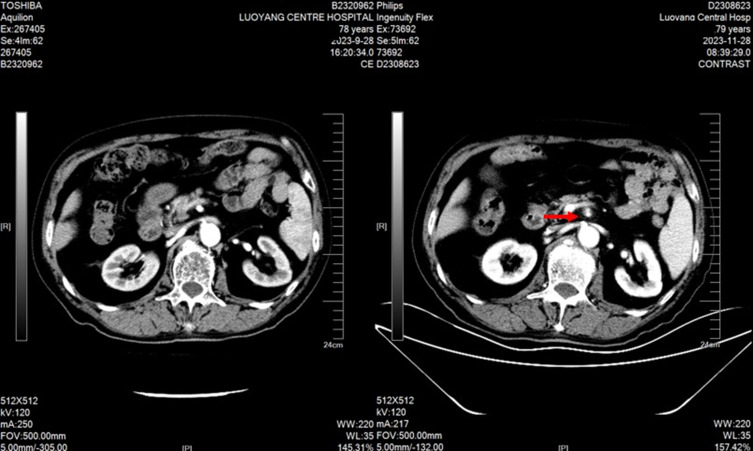

Background: Apatinib mesylate, a VEGFR2 tyrosine kinase inhibitor, is approved for advanced liver, esophageal, gastric and other malignant tumors, but its adverse effects require attention. We report a 79-year-old male with prostatic adenocarcinoma who developed superior mesenteric artery dissecting aneurysm after combined apatinib and chemotherapy. Apatinib, an anti-angiogenic agent, synergizes with chemotherapy. After informed consent, the combination regimen was initiated. Two cycles later, the patient had tolerable intermittent abdominal pain, and CT confirmed the aneurysm. Due to progressive tumor and poor physical status, no further treatment was given as the aneurysm did not affect the disease course. This case report aims to provide insights into the safe application of apatinib in clinical practice.

Case report: In this case report, a 79-year-old male with a height of 172 cms and a weight of 67 kgs who had been diagnosed with prostate adenocarcinoma for over three years. MRI scan indicated that bone metastases increased and enlarged compared with prior test. No significant abnormalities were observed in both physical and blood examinations. The pelvic MRI scan showed a prostatectomy changes, multiple abnormal signals in the bilateral ilium, acetabulum, femur, ischiatic bone, pubis, sacral vertebrae, and part of the lumbar vertebrae.